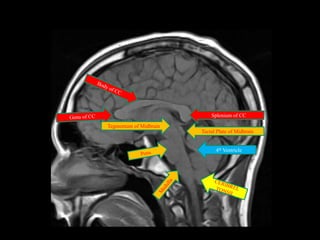

Splenium of CC

Tegmentum of Midbrain

Tectal Plate of Midbrain

4th Ventricle

Splenium of CC Tegmentumof Midbrain Tectal Plate of Midbrain 4th Ventricle